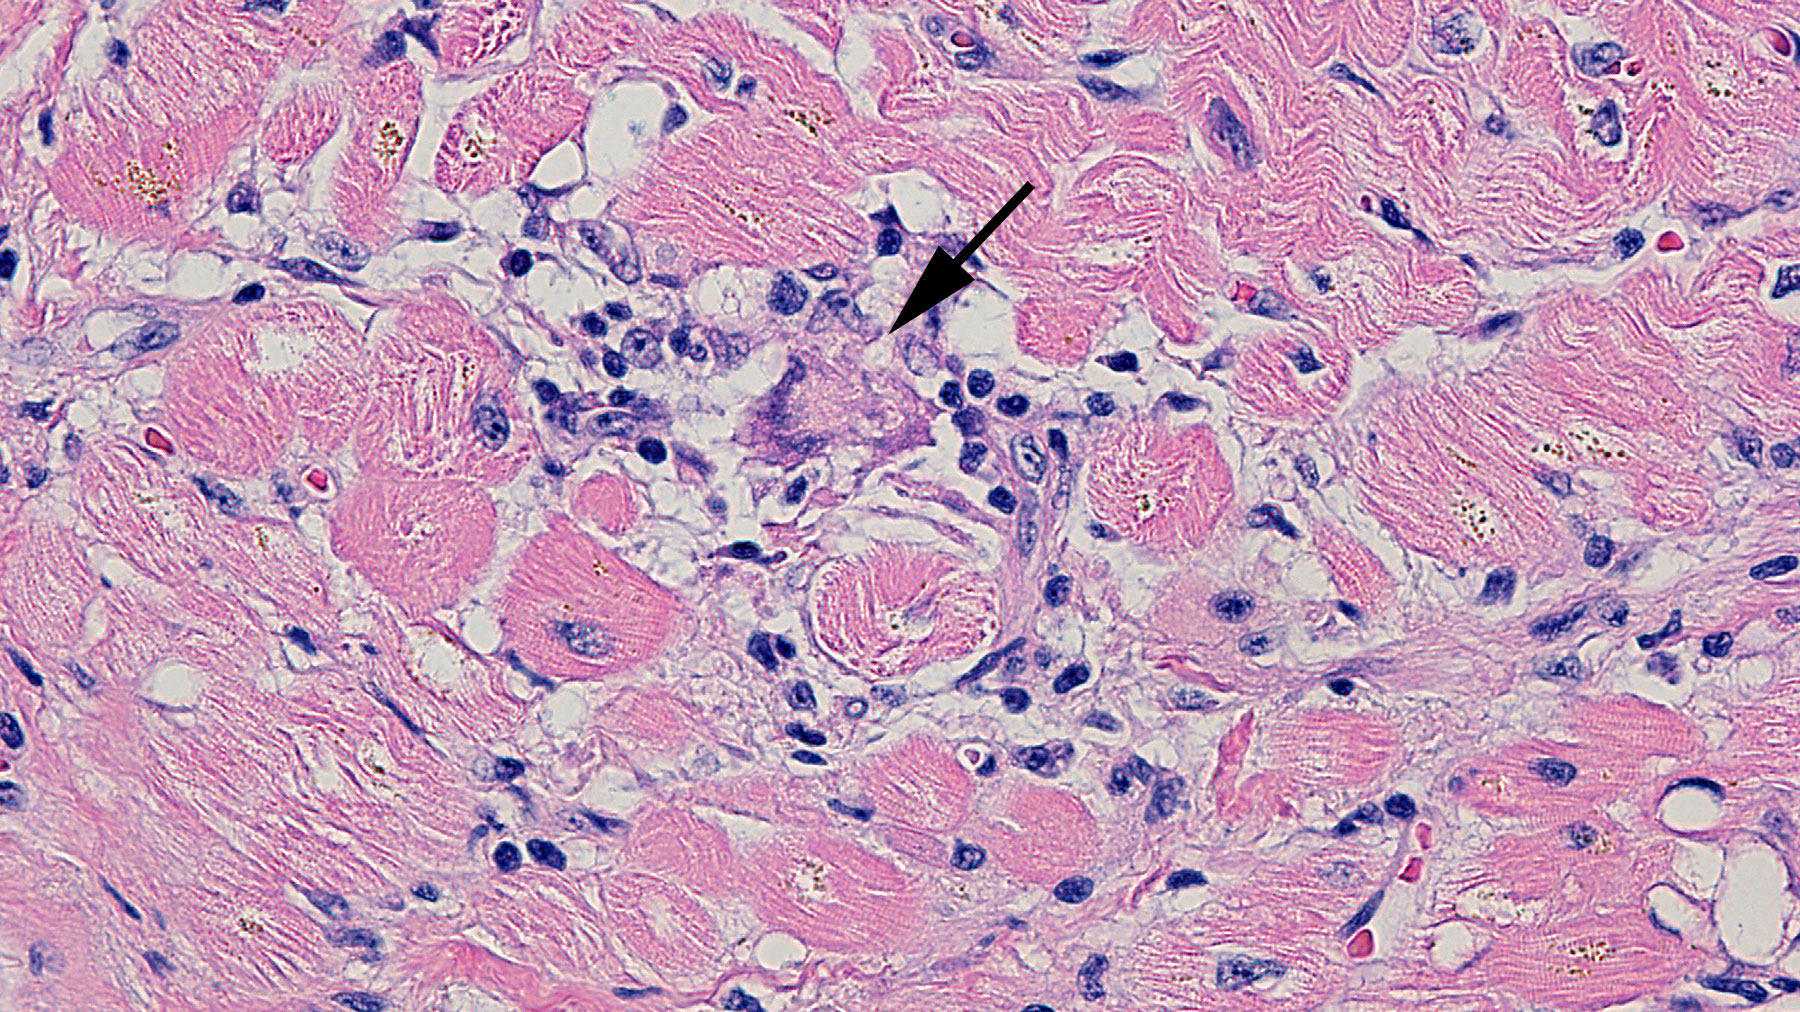

Giant Cell Myocarditis

Figure A: H&E staining (40x)

Clinical History: 63 year-old male with end stage non ischemic cardiomyopathy and severe heart failure underwent a heart transplant.

Histology: The above histological sections of myocardial tissue show multiple foci of mixed inflammation, interstitial fibrosis and occasional myocardial necrosis. The infiltrates are comprised of lymphocytes, macrophages, eosinophils, plasma cells, histiocytic aggregates and giant cells (arrow in figure A). Trichrome stain (Figure E) highlights the interstitial myocardial fibrosis.